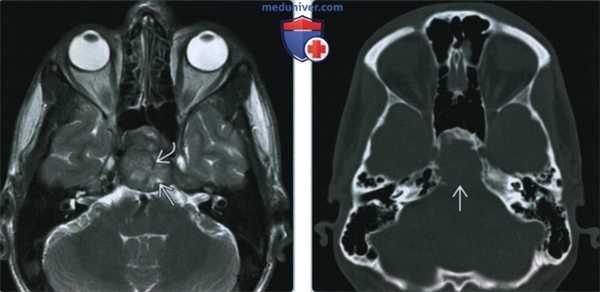

(Слева) При МРТ Т2ВИ в аксиальной проекции у этого же пациента регистрируется неоднородный средней интенсивности сигнал (опухоли) с участками более интенсивного сигнала, которые могут являться очагами некроза. Криволинейная низкоинтенсивная зона, вероятно, представляет собой участок кальциноза опухолевой ткани.

(Справа) При аксиальной КТ в костном окне у этого же пациента видно, что перед нами преимущественно литическая остеосаркома. Отмечается некоторое расширение ската затылочной кости, позади него определяется обширная зона деструкции кости. Остеоидного матрикса в ткани опухоли не наблюдается.